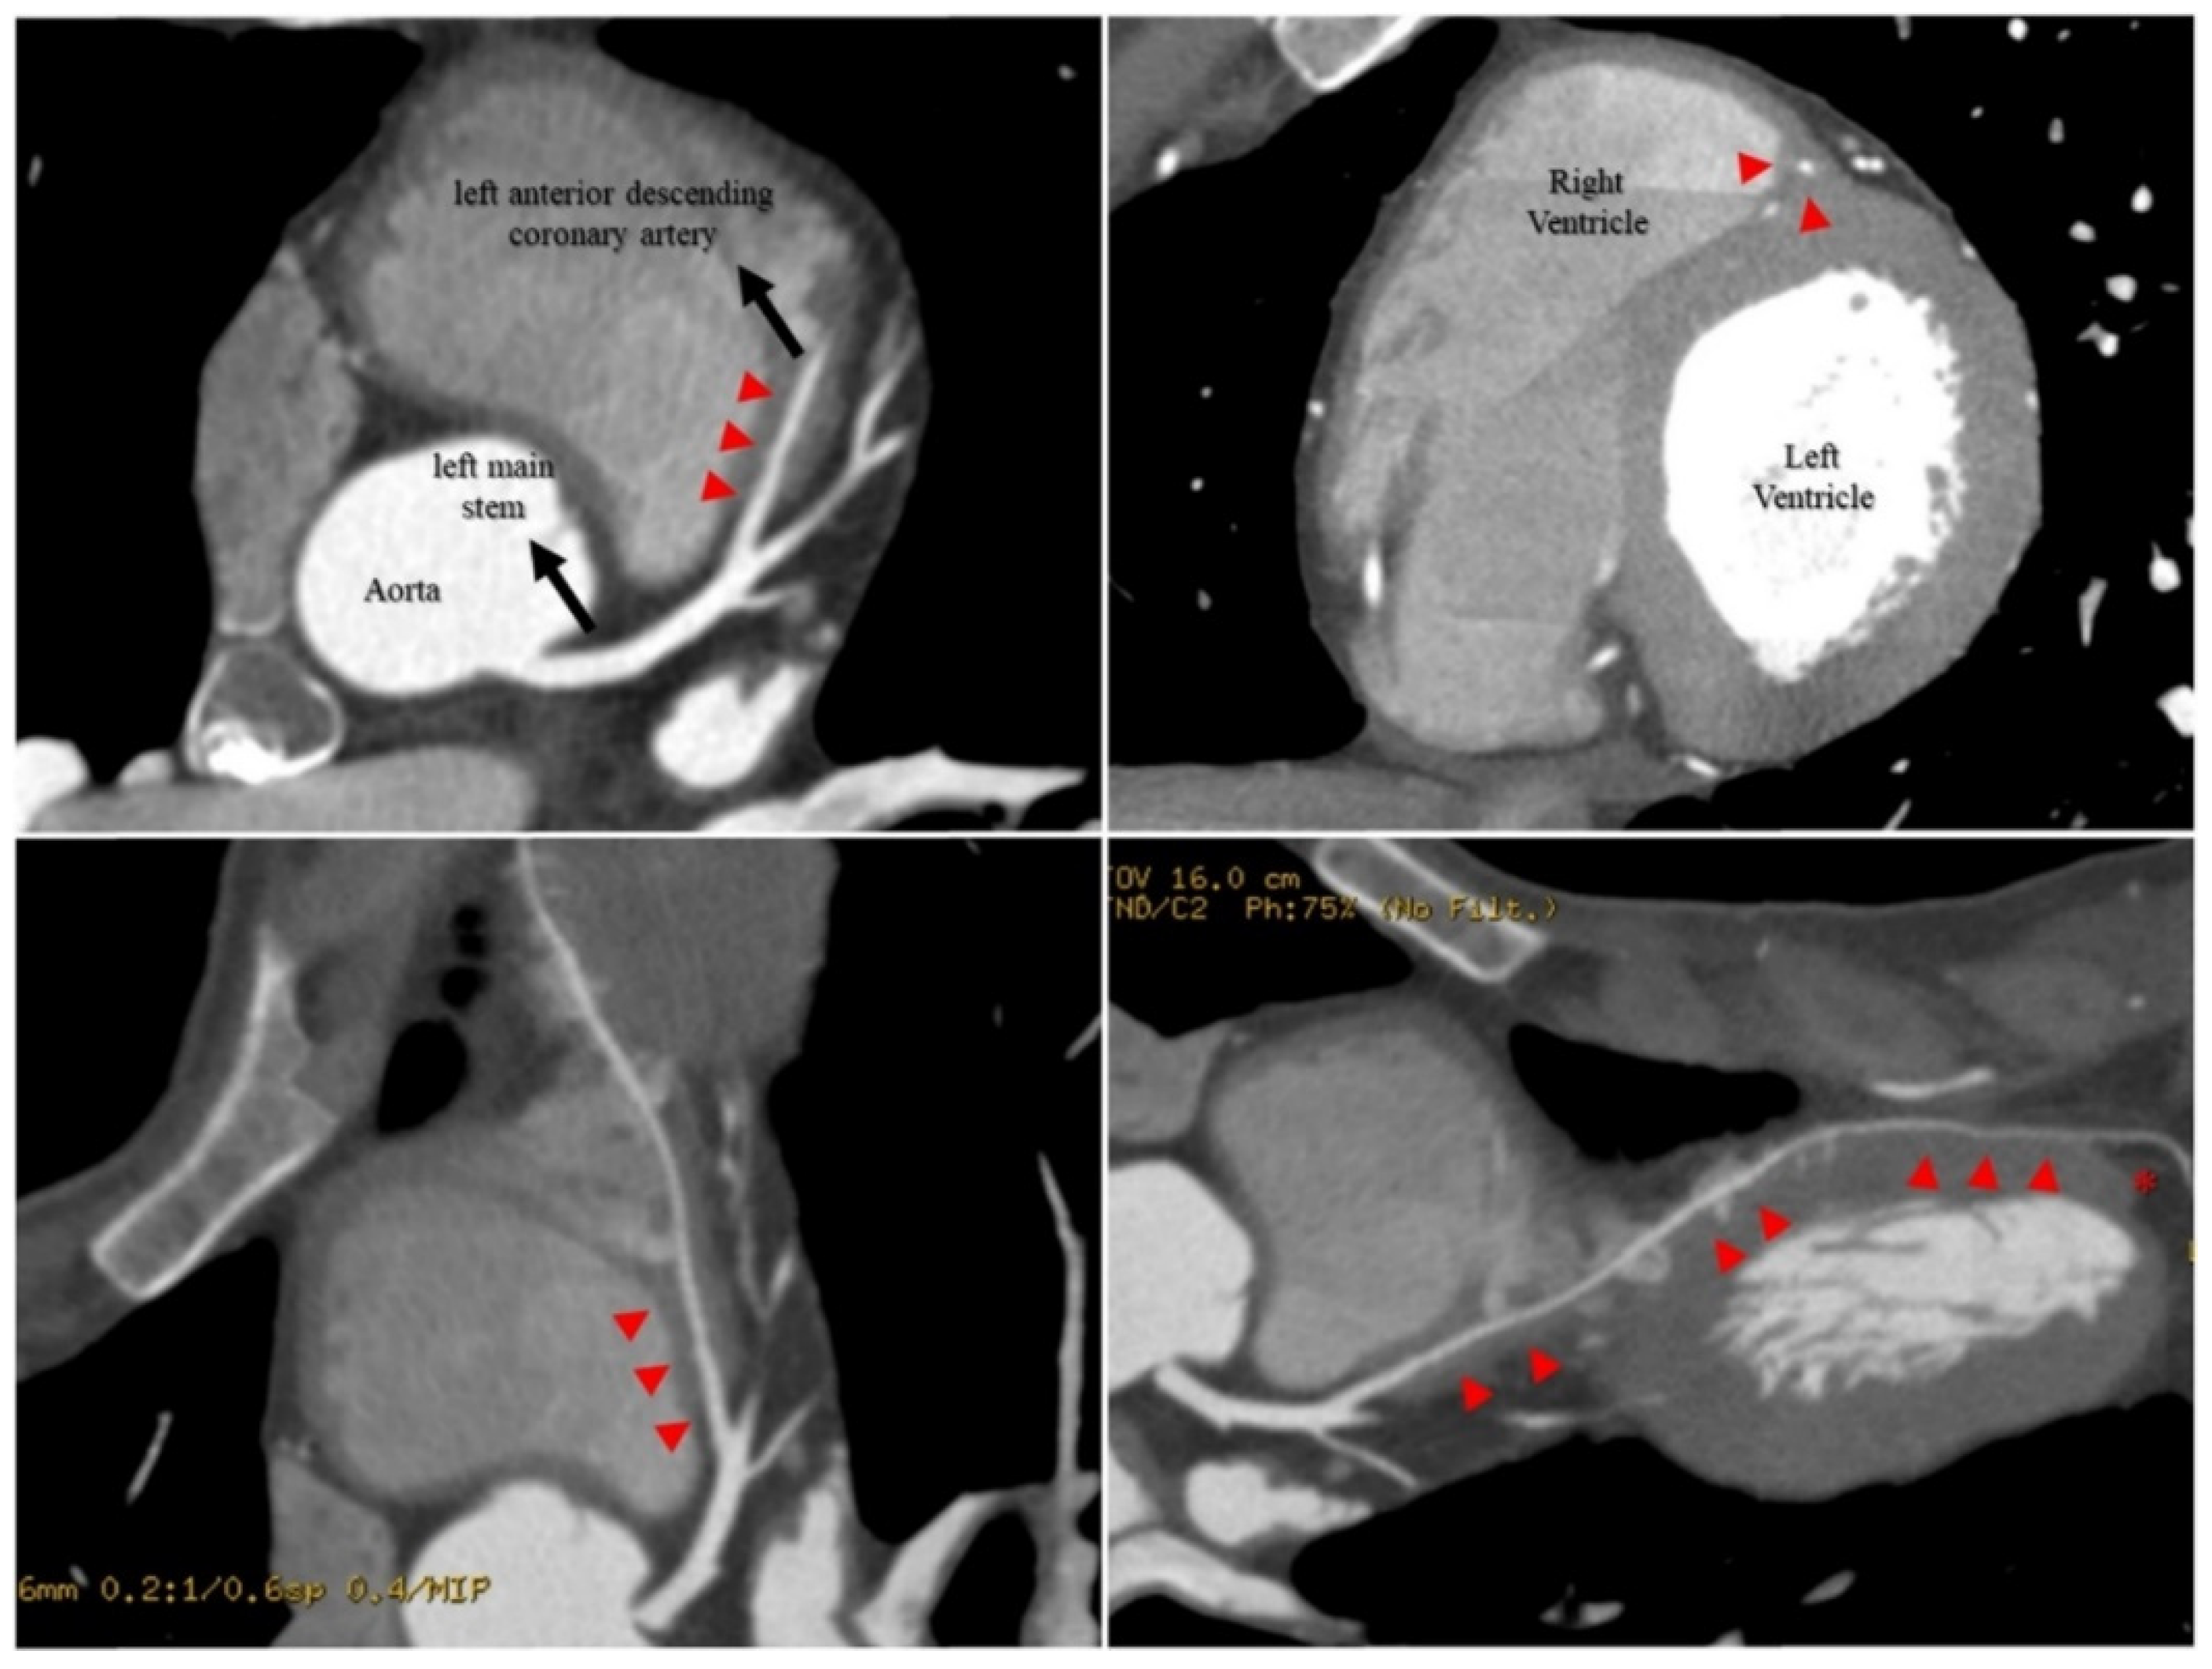

2.4. Investigations